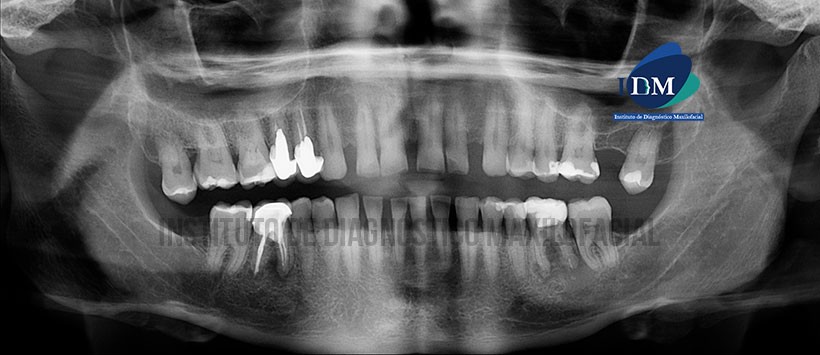

Paciente de 50 años de sexo masculino acude al Instituto de Diagnóstico Maxilofacial para evaluación imagenológica de la pieza 46.

A la evaluación de la radiografía panorámica evidenciamos una neumatización alveolar de ambos senos maxilares, faceta de desgaste coronario de todas las piezas compatible con atrición, presencia de diastemas en sector dentario anterior, múltiples restauraciones, material de obturación de conductos con espigo y corona protésica en piezas 14, 15 y 16, teniendo esta última procesos osteolíticos en zona apical de ambas raíces. Siendo lo más resaltante la presencia de una imagen radiolúcida localizada en zona apical de la pieza 46 y de limites parcialmente definidos compatible con proceso osteolítico, también se visualiza una restauración coronaria y cameral. (Figura 1)